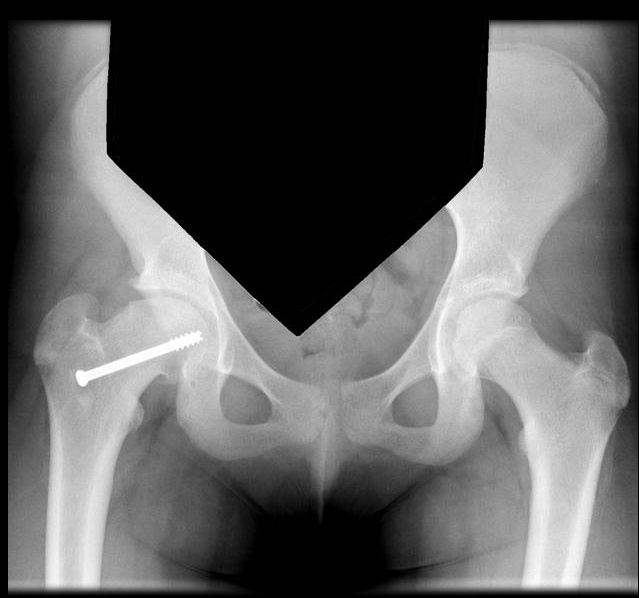

X-ray imaging including AP and frog leg lateral of both hips shows the epiphysis remaining within the acetabulum while the neck displaces anteriorly and externally rotates leaving the head posterior to the neck. An early radiographic finding is epiphysiolysis where the growth plate is widened or shows increased lucency.,

Treatment

Treatment options are primarily surgical with percutaneous pinning of the slipped side. Treatment of this condition is emergent.,

Prophylactic pinning of the non-slipped side should be considered in cases of slipped capital femoral epiphysis related to hypothyroidism.

Complications of slipped capital femoral epiphysis include avascular necrosis, chondrolysis, and premature osteoarthritis.